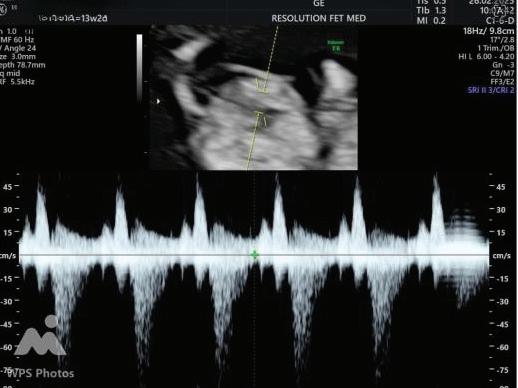

The first trimester— spanning from conception to 13+6 weeks—is no longer considered a “blind phase” of pregnancy. With the evolution of highresolution ultrasound, color Doppler and advanced biochemical screening, this period has transformed into a window of opportunity for early fetal evaluation, risk prediction and preventive strategies.

First-trimester fetal evaluation is not limited to dating the pregnancy or confirming viability—it is the foundation of predictive, preventive, and personalized obstetric care.

2. NUCHAL TRANSLUCENCY (NT) SCAN

• Done @11–13+6 weeks.

• CRL 45–84 mm.

• This is the cornerstone of first trimester screening.

1. NT is the sonographic appearance of subcutaneous accumulation of fluid behind the fetal neck, below the skin in the first trimester of pregnancy.

2. Measured in mid-saggital section only.

3. Measured between 11-14 weeks.

4. CRL between 45-84mm.

5. Magnified to include only head and upper thorax.

6. Fetus should be in neutral position.

7. Demostrate fetus separate from amnion.

8. Measurement should be ON to ON (cross bar of the callipers should be such that it’s hardly visible and merges with white line, not nuchal fluid).

During the scan more than one measurement should be taken and maximum value should be considered.

ADDITIONAL SONOGRAPHIC MARKERS:

A Wave Reversal

MARKER

Ductus Venosus flow

Tricuspid Regurgitation

Tricuspid Regurtitation

SIGNIFICANCE

Reversed a-wave in aneuploidy or cardiac dysfunction

Suggests cardiac abnormality or aneuploidy